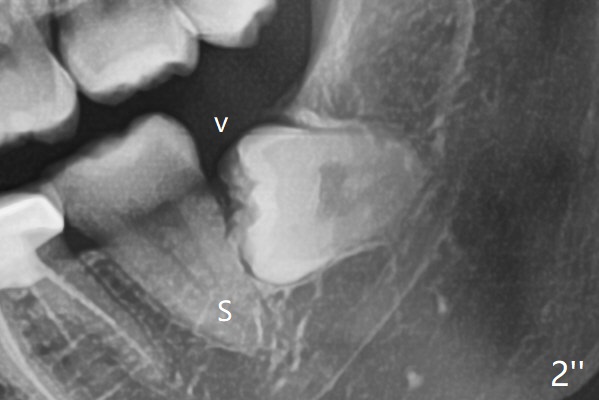

A 31-year-old woman returns with chief complaint of "occasional, mild pain in the lower left 3rd molar" 1 year post extraction of #1 and 16 (Fig.1,2). The lower 2nd molars appears to have a single fused root (Fig.2',2'' S); the radiopaque image mesial to the tooth #32 must be the dense bone (Fig.2' *). In contrast the cortex coronal to the tooth #17 is lacking (Fig.2'' v), as compared to that in Fig.2'. It seems that the bone loss at #17 is associated with mild pericoronitis. The tooth #17 should be extracted with placement of Bond Apatite to repair #18 distal defect. In fact sticky bone and collagen plug are placed instead (Fig.3), covered by 2 pieces of PRF.